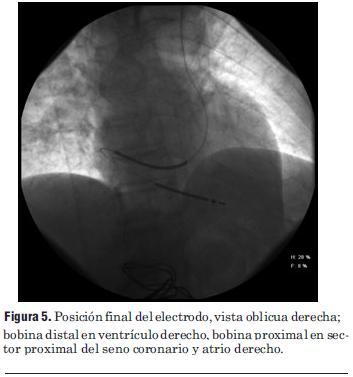

El implante se realizó vía subclavia izquierda. Durante el procedimiento se observó que luego de puncionar la vena y al introducir la guía, la misma no avanzaba libremente; con fluoroscopía se aprecia que la guía avanza reiteradamente hacia la vena yugular izquierda, no pudiéndose dirigir, como se practica habitualmente, hacia la vena cava superior del lado derecho, a pesar de reiterados intentos. Se procedió entonces a realizar venografía (figura 4), encontrándose la presencia de una vena cava superior izquierda sin comunicación con el lado derecho, la que drena en un seno coronario muy dilatado desembocando en la aurícula derecha. Definida la anatomía y utilizando introductor 11 Fr tipo peel away se coloca catéter electrodo de fijación pasiva, con dos electrodos en su extremo para estimulación (bipolar) y con dos bobinas para desfibrilación (Linox TD 75/16 Biotronik®). Retirado el introductor y utilizando guías apropiadas, a las cuales se preforma con curvas adecuadas que faciliten acceder al ventrículo derecho, se maniobra el catéter con movimientos de avance, retroceso y rotación hasta lograr introducirlo en el mismo. Una vez allí y utilizando otra guía con una curva apropiada preformada se maniobra hasta lograr posicionar los electrodos distales a nivel del ápex del ventrículo derecho (figuras 5 y 6). El umbral de estimulación fue de 0,1 mV a 0,5 ms de ancho de pulso y la onda R medida de 16 mV. Se procede posteriormente a la fijación del electrodo de la forma habitual y a conectar e implantar el cardiodesfibrilador (Lexos VR, Biotronik®) en bolsillo prepectoral. Para finalizar se realiza test de desfibrilación: inducción de fibrilación ventricular mediante choque sobre T, que es correctamente sensada e interrumpida por el dispositivo con choque de 20 J. Tiempo del procedimiento 65 minutos; tiempo de fluoroscopía 7 minutos. No hubo complicaciones y el paciente fue dado de alta 24 horas después.

Figura 5. Posición final del electrodo, vista oblicua derecha; bobina distal en ventrículo derecho, bobina proximal en sector proximal del seno coronario y atrio derecho.